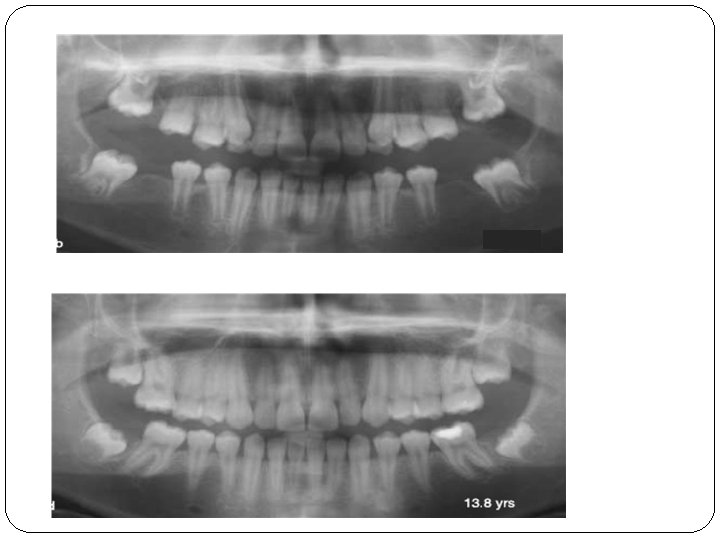

Evaluation of spontaneous space closure and development of permanent dentition after extraction of hypomineralized permanent first molars BIRGITTA JÄLEVIK & MARIE MÖLLER Twenty-seven children who had one to four permanent first molars extracted due to severe MIH. Each case was followed up on individual indications 3. 8– 8. 3 (median 5. 7) years after extractions. The eruption of the permanent dentition, and space closure were documented by orthopantomograms, casts, photographs, and/or bitewings. Fifteen children were judged to have a favourable spontaneous development of their permanent dentition without any orthodontic intervention. Seven children were or should be subjected to orthodontic treatment for other reasons registered prior to the extraction. Five International children were Journal judged of to Paediatric have a treatment at least caused by 2007 the extractions, but three of them Dentistry

7. 7 8. 8 7, 7 10. 2 13. 8 International Journal of Paediatric